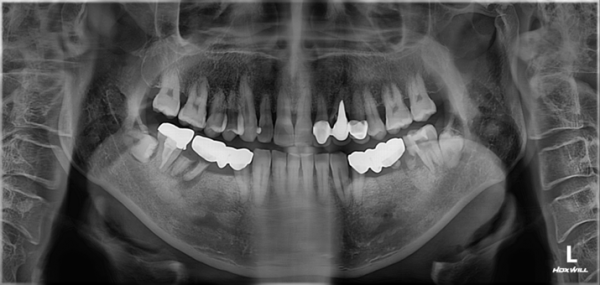

임플란트 양쪽 어금니 임플란트 치료 #2

임플란트 양쪽으로 총 4개를 식립하여

다시 식사가 가능한 상태로 치료를 마무리 하였습니다.

촬영시기 : 22.03.29(전), 22.10.11(후)